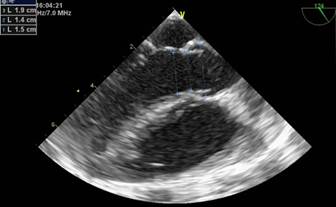

La reconstrucción 3D muestra un defecto alargado de 5 por 10 a 11 mm con presencia de membrana que lo tabica parcialmente, (Figura 6)